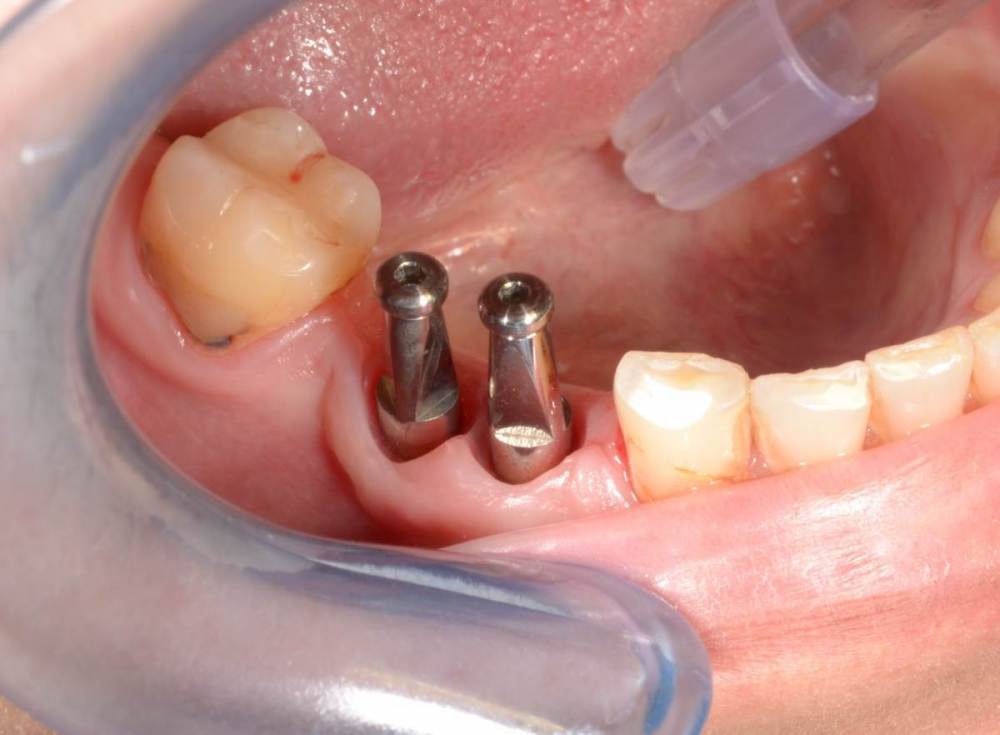

Большой Зеленый Опубликовано 27 мая, 2022 Поделиться Опубликовано 27 мая, 2022 Аналогично..) 4 1 Ссылка на комментарий

Большой Зеленый Опубликовано 27 мая, 2022 Поделиться Опубликовано 27 мая, 2022 Через 9 лет. Есть немного рецессии.. 2 Ссылка на комментарий

Большой Зеленый Опубликовано 27 мая, 2022 Поделиться Опубликовано 27 мая, 2022 4 часа назад, pit сказал: Это связано исключительно с вестибулярной позицией импланта. Это как раз к вопросу про те минимальные 2мм до вестиболярной стенки, вне зависимости есть она или ты ее создаешь. С тех пор я стал хитрее умнее и опытнее ))) 1 час назад, alboard сказал: А в чем смысл ее сохранности, если препарируя под имплантат вы все равно ее в большинстве случаев сносите? Первичная стабильность импланта зачастую достигается только перегородкой.. Ссылка на комментарий

Большой Зеленый Опубликовано 28 мая, 2022 Поделиться Опубликовано 28 мая, 2022 12 часов назад, Женька сказал: @Большой Зеленый это вроде ваш старый кейс? напомните пожалуйста, тут присыпка+мембранинг вестибулярно и вестибулярным лоскутом слегка послабленным всё закрыли? Да все так и есть как Вы и описали. Работе почти 10 лет. Присыпка мп3 от остеобила сверху "ильгамовская" губка . Считаю что результат вполне удовлетворительный. Рецессия обусловлена как уже сказали выше вестибулярным положением импланта ,ну и недозаглублен чуток. Ссылка на комментарий